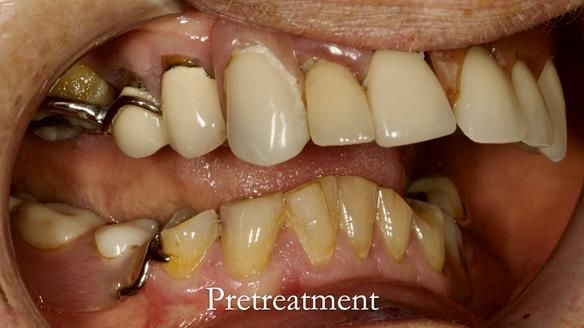

Aesthetically and functionally poor RPDs were replaced for Eileen, a 74 year old woman.

Referred to me by her general dental practitioner specifically for replacement RPDs.

Dental concerns

“Top denture loose making conversation difficult at times. Also, appearance isn’t good. Teeth uneven”

Diagnoses

- Missing teeth in the upper and lower jaws

- Upper and lower metal based RPDs, poorly fitting, worn occlusal surface, reverse curve aesthetics, lacking support

- Poor dental appearance with reverse incisal curve

- The upper right central and lateral incisors with post crowns. Healthy and functionally secure but with poor appearance, contributing to the reverse curve.

- Moderate to heavily restored dentition with deep overbite (Class 2 div II)

- Yellowish lower front teeth with small amount of wear.

- The lower right canine (LR3) is worn with MOD cavity.